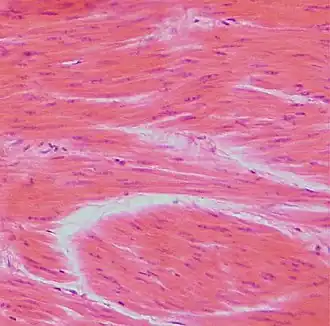

Гладко-мышечная ткань, гематоксилин-эозин.

У некоторых беспозвоночных гладкие мышцы образуют всю мускулатуру тела. У позвоночных они входят в состав оболочек внутренних органов: кишечника, кровеносных сосудов, дыхательных путей, выделительных и половых органов, а также многих желёз. Клетки гладких мышц у беспозвоночных разнообразны по форме и строению; у позвоночных в большинстве случаев веретенообразные, сильно вытянутые, с палочковидным ядром, длиной 50—250 мкм, в матке беременных животных — до 500 мкм; окружены волокнами соединительной ткани, образующими плотный футляр.

Мышечные клетки называются миоцитами. Гладкие миоциты — веретенообразные вытянутые клетки, содержащие одно палочковидное ядро, расположенное в центре. Каждый миоцит окружён базальной мембраной[3].